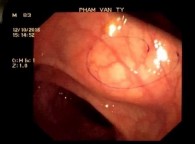

bệnh được soi dạ dầy tá tràng cao 407/557 (73%), trong tổng số vị trí u tại thực quản, dạ dày, tá tràng là 319 ca thì tỉ lệ phát hiện qua nội soi ống mềm là 78% (249/319), tại trực tràng, đại tràng và manh tràng là 73% (66/91). Tỉ lệ phát hiện qua soi ống mềm không thể đạt được 100% do u không thuộc biểu mô phát triển từ thành ống tiêu hóa chứ không phải từ lớp niêm mạc nên hình ảnh nội soi thường thấy giống như khối đè đẩy từ ngoài vào. Tổn thương thường được bao phủ bởi một lớp niêm mạc bình thường, đôi khi có thể có loét, tăng sinh mạch hay chảy máu do u chèn ép gây thiếu máu cục bộ vùng niêm mạc ở vị trí tương ứng. Hình ảnh nội soi chỉ mang tính chất gợi ý chứ không thể phân biệt được bản chất của u với các tổn thương ngoài niêm mạc như u lympho, u cơ trơn, GIST …

Hình 4.1. Hình ảnh trên nội soi ống mềm: u cơ vân tại đại tràng trái (A), u cơ trơn tại thực quản (B), u hắc tố ác tính tại trực tràng (C)